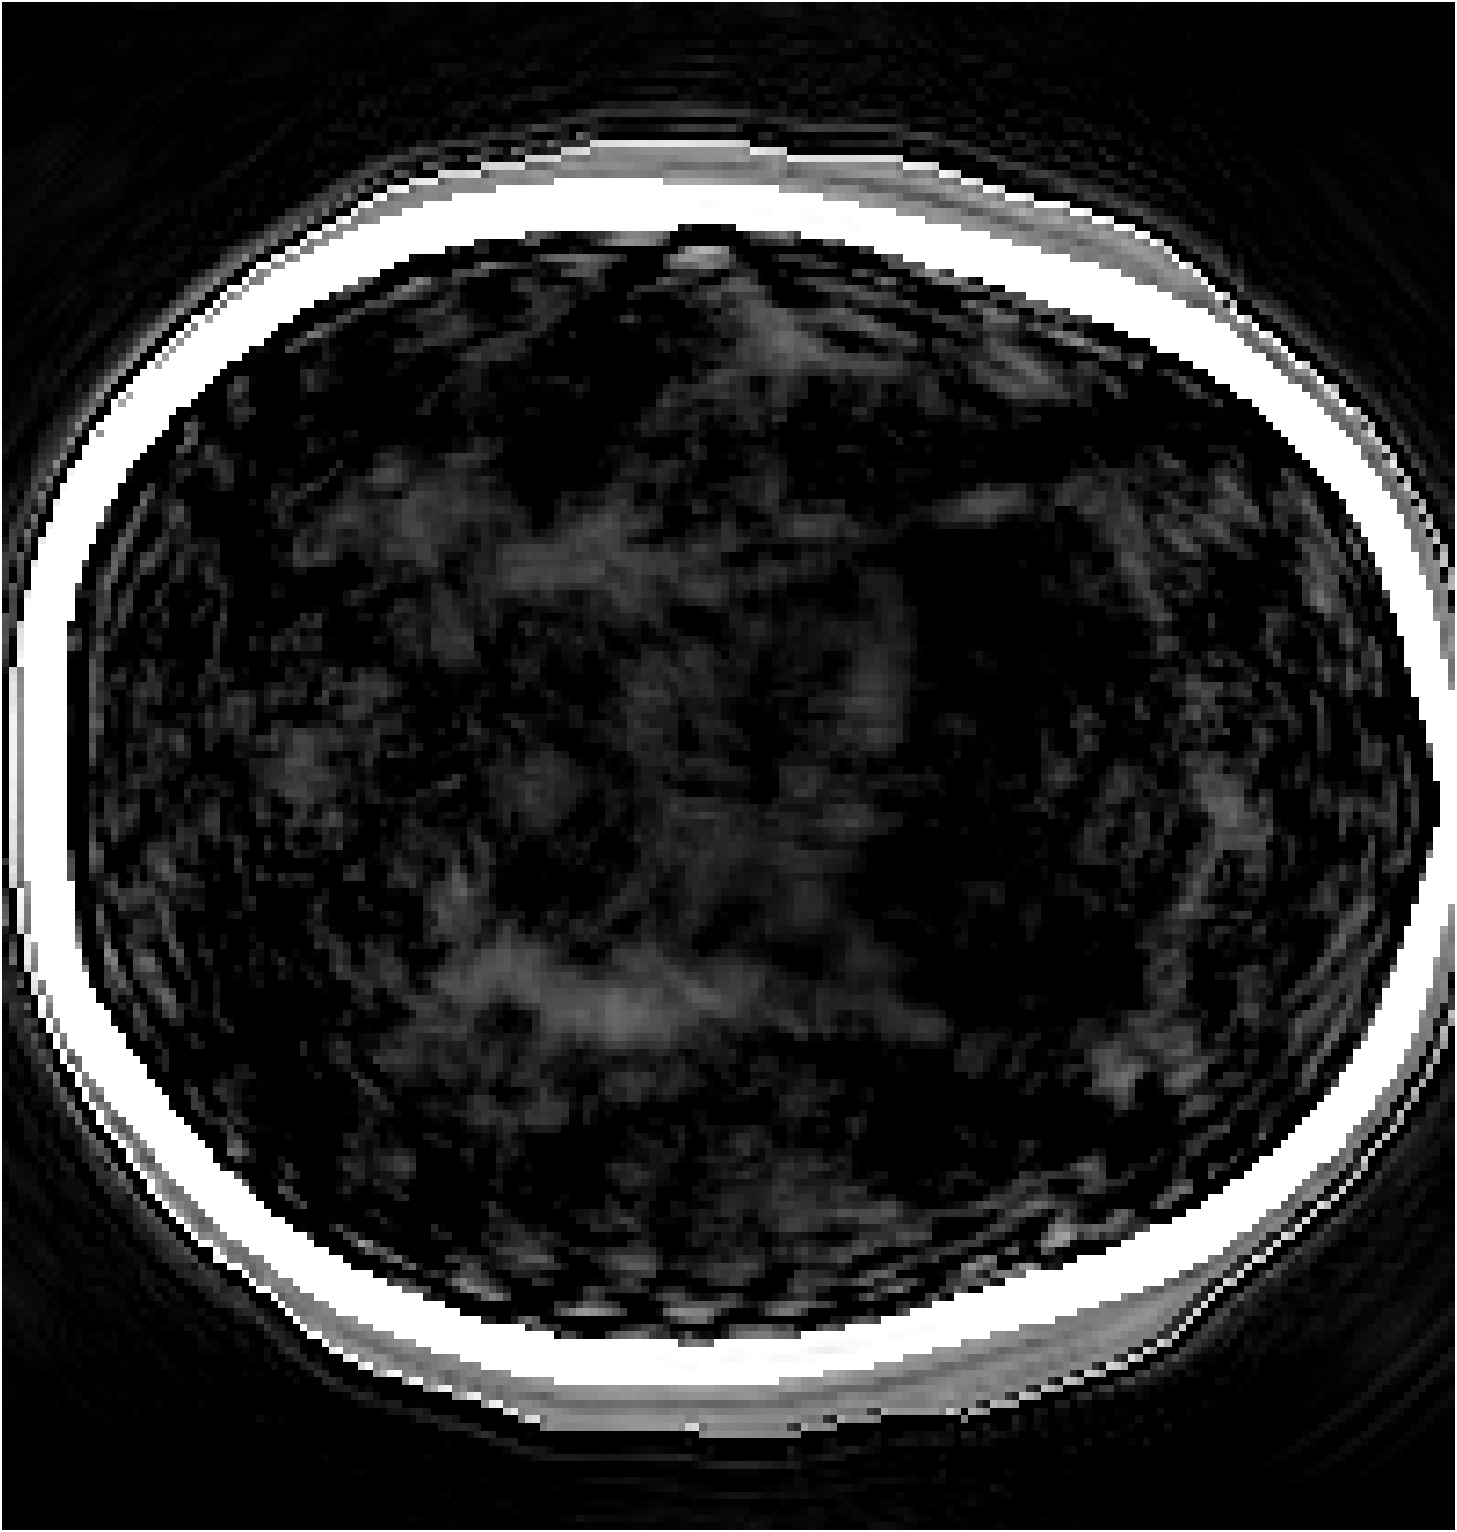

Figure 8: Comparison between physics-based FWI and the proposed BrainPuzzle reconstruction. (a) Homogeneous initial SoS; (b) FWI result using homogeneous initial model; (c) Smoothed initial SoS; (d) FWI result using smoothed initial model; (e) BrainPuzzle SoS reconstruction; (f) Ground truth. BrainPuzzle yields accurate and detailed structures even without a high-quality initial model.

Additionally, we also compare BrainPuzzle with the physics-based FWI with results illustrated in Figure 8. The physics-based FWI is conducted using the steepest descent method over 30 epochs with the full-transducer dataset. We use two different initial models: one with a homogeneous velocity assigned to all tissues inside the skull (Figure 8(a)), and the other obtained by smoothing the ground-truth tissue distribution within the skull (Figure 8(b)). The model with a homogeneous initial condition produces poor results, while the one with a smoothed initial model yields much better outcomes, indicating that the physics-based method relies heavily on the accuracy of the initial guess of SoS. In contrast, Brain Puzzle SoS achieves good results even with the partial-transducer setup as shown in Figure 8(e).